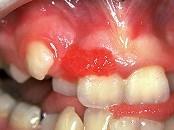

问题 组图是牙龈瘤患者,有关此病的描述不正确的是 ( )

选项 A.可能导致牙松动 B.可破坏牙槽骨壁 C.肿块较局限 D.生长较慢 E.为恶性病变

答案 E